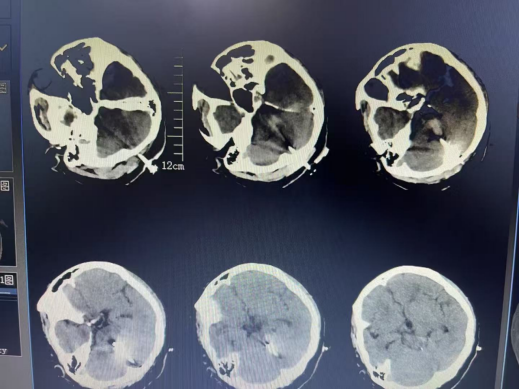

家住呼兰区45岁的张女士(化名),在家中突发意识不清,进行性加重,伴有呼吸困难。被家人紧急送往当地医院急诊科行头部CT检查后,显示脑干出血,约7毫升,并压迫脑干等重要结构。密切观察治疗过程中,突发呼吸骤停,给予心肺复苏后恢复自主呼吸心跳。生命体征稳定后,为求进一步诊治,乘救护车转院来到哈医大四院寻求诊治。哈医大四院神经外科詹奇副主任医师接诊后,完善术前相关检查,详细评估患者病情后,向患者家属交代病情后,决定采用机器人辅助定位下进行脑干出血手术治疗。

术前头部三维CT成像。

术后第一天复查头部CT。

术后一周复查头部CT。